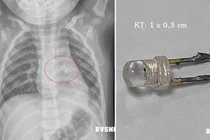

Hóc dị vật đường thở là một tai nạn cực kỳ nguy hiểm và thường xảy ra, đặc biệt khi trẻ đang ăn uống một thứ gì đó. Nếu không được sơ cứu kịp thời và đúng cách sẽ gây ra nhiều biến chứng, thậm chí có thể tử vong.

Dị vật đường thở có thể gây một số biến chứng nguy hiểm như viêm phổi, tràn khí màng phổi, viêm trung thất,.. thậm chí có thể tử vong nếu không xử trí kịp thời để đưa dị vật ra ngoài.